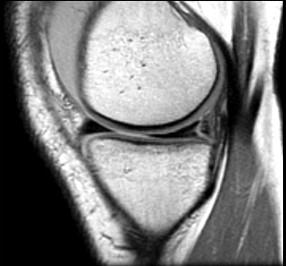

问题 男,32岁,左膝关节有外伤史,膝关节部有疼痛,上下楼梯时加重,请结合所提供的图像,选择最佳选项 ( )

选项 A、胫骨骨折 B、后十字韧带撕裂 C、前十字韧带撕裂 D、内侧半月板外周后角垂直撕裂 E、未见异常

答案 D